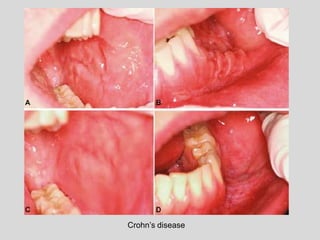

• Crohn’s disease

Crohn’s disease Ulcerative colitis

Granuloma Microabscessus

Crohn’s disease